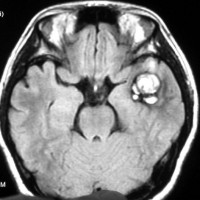

海綿状血管腫はMRIの撮影条件によっていろいろな見え方をします

腫瘍から少し出血したために,患者さんはけいれん(てんかん発作)を起こしました。左のT1強調画像では出血を疑います。中央のT2強調画像では海綿状血管腫の周りに脳浮腫があるために白くぼやけた部分があります。右の造影剤を使ったMRIでは造影剤が入るところがほどんど無いことがわかります。側頭葉の海綿状血管腫は側頭葉てんかんという症状で発症することが多いです。

出血が溶けて少し小さくなっています。海綿状血管腫の周りには黒い縁取りがあります。この黒い部分は血液が溶けて残った鉄が脳の中にたまったことを示しています(siderosisといいます)。この鉄のしみ込みはけいれんの原因になると考えられます。この海綿状血管腫は中等度の大きさですが,治療が難しいほどのてんかんが無ければ手術などしないでほっておいてもいいです。手術で側頭葉(特に海馬)を損傷すると記憶の障害などもでます。